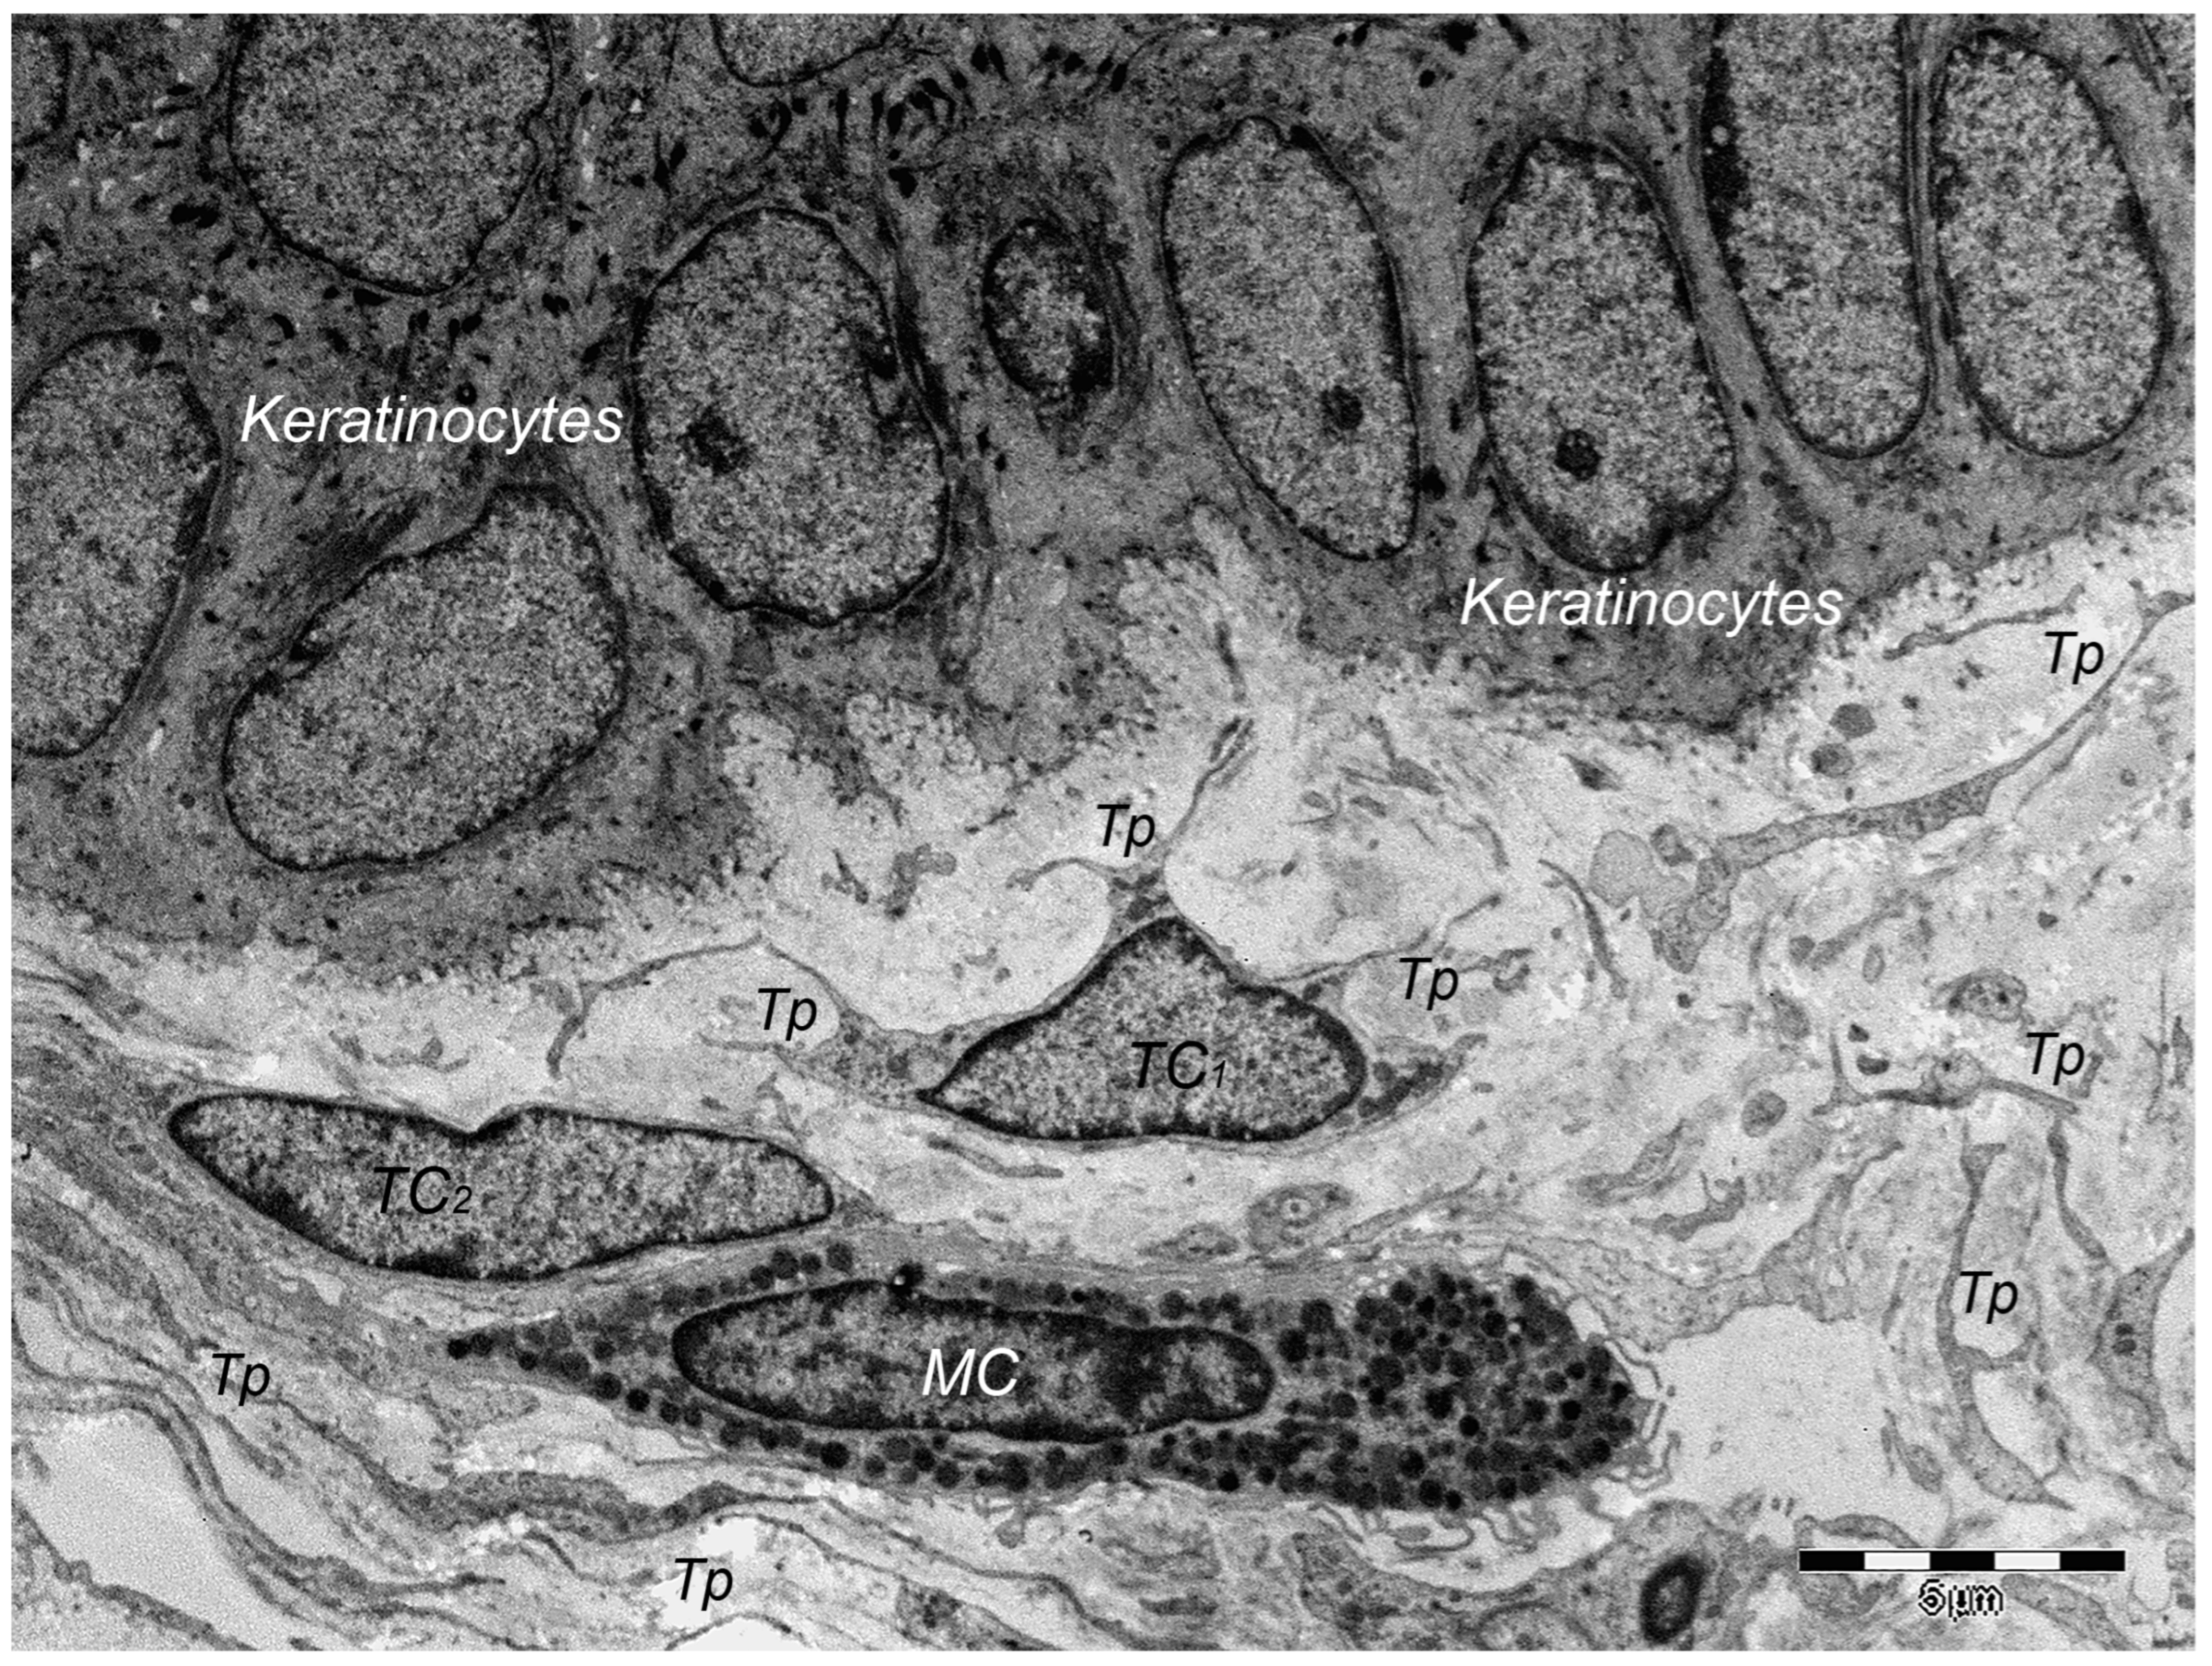

9. Dermal TCs: A Distinct Cell Population with a Promising Skin Regenerative Potential

- Rusu, M.C.; Mirancea, N.; Mănoiu, V.S.; Vâlcu, M.; Nicolescu, M.I.; Păduraru, D. Skin Telocytes. Ann. Anat.—Anat. Anz. 2012, 194, 359–367. [Google Scholar] [CrossRef] [PubMed]

- Manole, C.G.; Soare, C.; Ceafalan, L.C.; Voiculescu, V.M. Platelet-Rich Plasma in Dermatology: New Insights on the Cellular Mechanism of Skin Repair and Regeneration. Life 2023, 14, 40. [Google Scholar] [CrossRef] [PubMed]

- Romano, E.; Rosa, I.; Fioretto, B.S.; Lucattelli, E.; Innocenti, M.; Ibba-Manneschi, L.; Matucci-Cerinic, M.; Manetti, M. A Two-Step Immunomagnetic Microbead-Based Method for the Isolation of Human Primary Skin Telocytes/CD34+ Stromal Cells. Int. J. Mol. Sci. 2020, 21, 5877. [Google Scholar] [CrossRef] [PubMed]

- Wang, L.; Xiao, L.; Zhang, R.; Jin, H.; Shi, H. Ultrastructural and Immunohistochemical Characteristics of Telocytes in Human Scalp Tissue. Sci. Rep. 2020, 10, 1693. [Google Scholar] [CrossRef] [PubMed]

- Mirancea, N.; Moroşanu, A.-M.; Mirancea, G.-V.; Juravle, F.D.; Mănoiu, V.S. Infrastructure of the Telocytes from Tumor Stroma in the Skin Basal and Squamous Cell Carcinomas. Rom. J. Morphol. Embryol. 2013, 54, 1025–1037. [Google Scholar] [PubMed]

- Díaz-Flores, L.; Gutiérrez, R.; Pino García, M.; González, M.; Díaz-Flores, L.; Francisco Madrid, J. Telocytes as a Source of Progenitor Cells in Regeneration and Repair through Granulation Tissue. Curr. Stem Cell Res. Ther. 2016, 11, 395–403. [Google Scholar] [CrossRef]

- Díaz-Flores, L.; Gutiérrez, R.; García, M.P.; González-Gómez, M.; Rodríguez-Rodriguez, R.; Hernández-León, N.; Díaz-Flores, L.; Carrasco, J.L. Cd34+ Stromal Cells/Telocytes in Normal and Pathological Skin. Int. J. Mol. Sci. 2021, 22, 7342. [Google Scholar] [CrossRef] [PubMed]